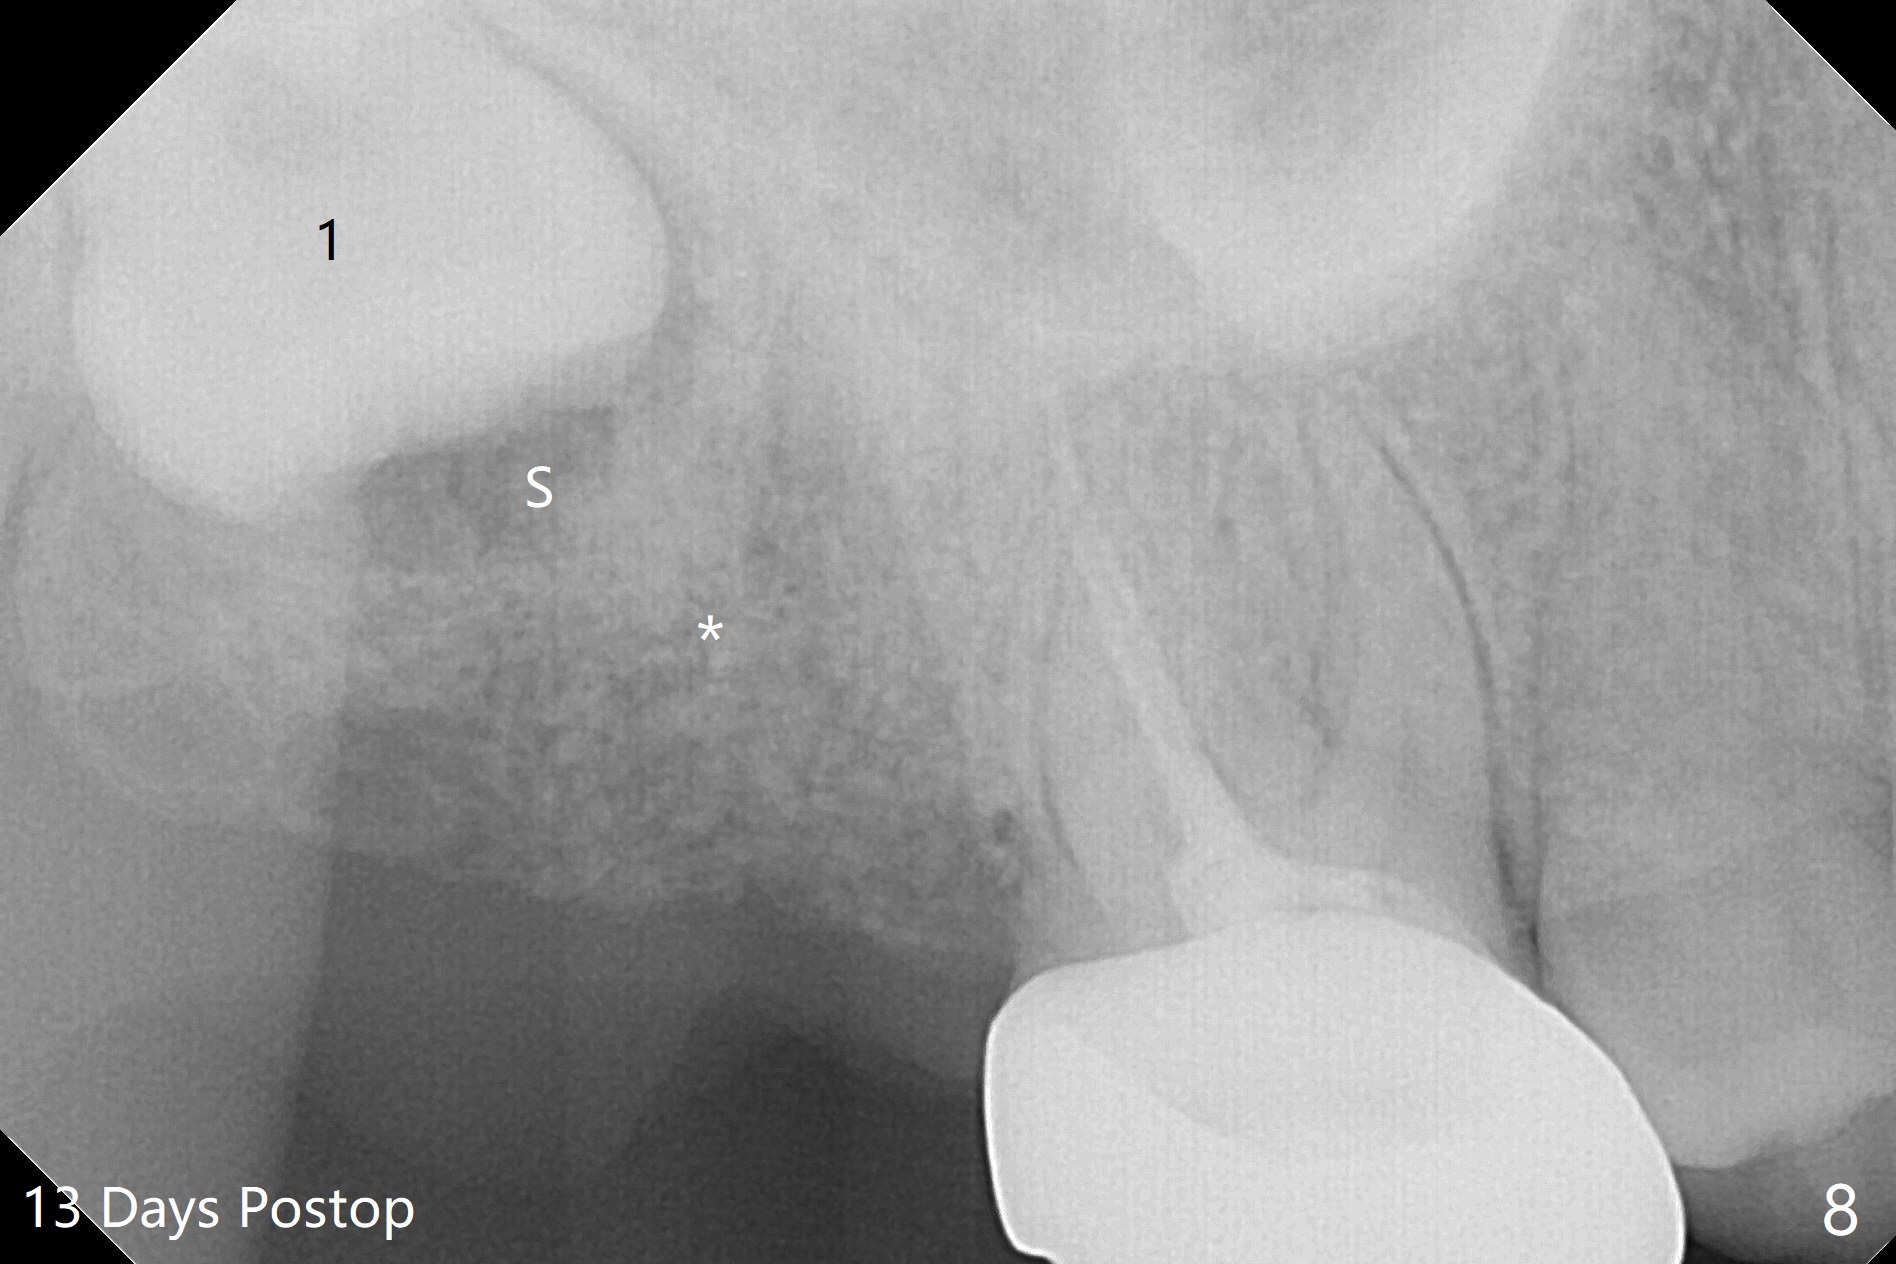

The socket of #2 heals 13 days postop; it appears that the bone graft remains in place (Fig.7,8 *). The patient is instructed to return in 3-4 months for impression and CT for guide. The socket heals 4 months postop (Fig.9,10). She plans to have implant next year, since she wants to add another insurance. The patient returns for implant without removal of the third molar 2 years 4 months post socket preservation (Fig.11). A 5x7.3 mm implant can be placed without invading the sac of the impacted third molar (Fig.12). In fact the lab has a better plan. A lump of bone forms in the previous socket 1 year 4 months postop (Fig.13 *). The ridge is wide and dense (Fig.14). A narrow implant placed oblique could be longer (Fig.15), as compared to a wide, short one (Fig.12).